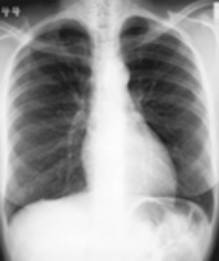

Dit is het meest uitgevoerde onderzoek op de dienst radiologie. Een thoraxfoto kan om veel redenen worden aangevraagd.

Als routine onderzoek bij een screening vb.

arbeidsgeneeskunde, pre- en post operatief |

Bij vermoeden van een longletsel |

Bij kortademigheid |

Als opvolging van het effect van een behandeling |

Bij een trauma van de borstkas |

Er zijn in princiepe twee manieren om een thorax opname te maken:

De

staande opname waar meestal een face en een profiel opname wordt

genomen |

liggende opname bij een patiënt die niet kan staan, normaal enkel

face opname tenzij anders aangevraagd |